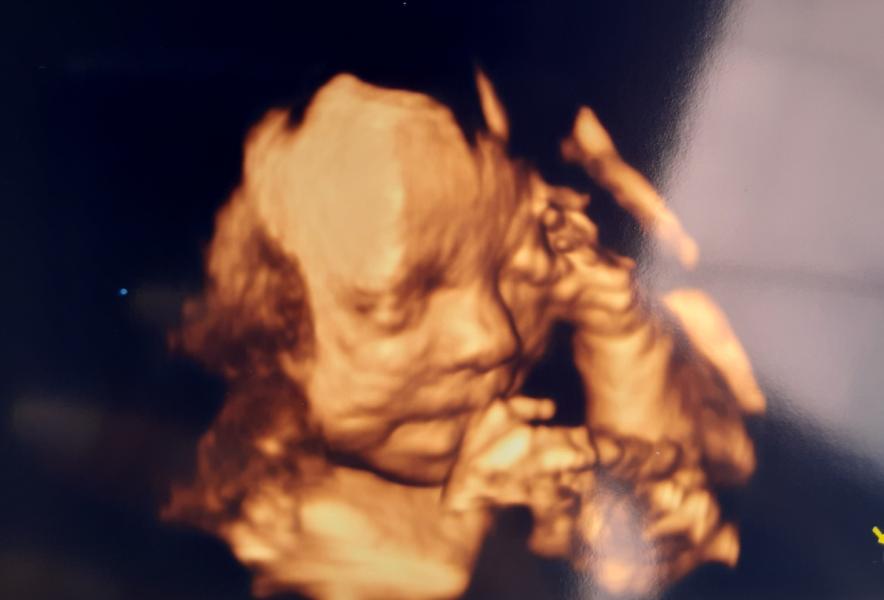

Моя малышка🥰 Кажется, похожа на папу. Очень активная, особенно реагирует на музыку🎶

Мы тоже сегодня делали 3д узи :) так интересно, на кого малышка будет похожа, когда родится :)

Они такие чудные в этой Д проекции 😂